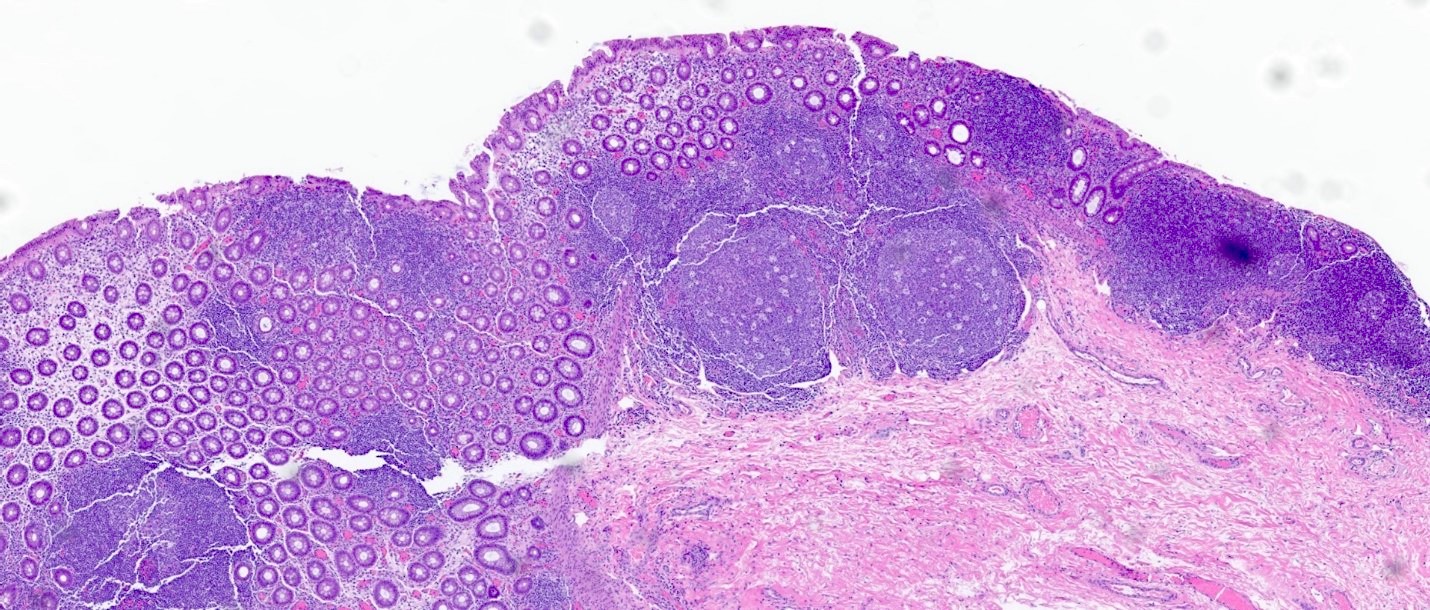

Contributed by Catherine E. Hagen, M.D. and Dustin W. Parsons, M.D.

Prominent lymphoid follicles Prominent lymphoid follicles Prominent lymphoid follicles

Prominent lymphoid follicles

A 72 year old man with a history of colon cancer undergoes radiation therapy, followed by partial colon resection with construction of an ileostomy. He denies any history of inflammatory bowel disease. The image shown above demonstrates histologic findings of the resected portion of the colon. These findings are most consistent with which clinical presentation?

A. Diversion colitis. The construction of an ileostomy should always raise suspicion for the possibility of diversion colitis. The prominent lymphoid aggregates are likely the most characteristic finding associated with diversion colitis. Other features appreciated here include patchy hypertrophy of muscularis mucosa, ulceration and loss of colonic crypts. Answer B is incorrect because the clinical vignette does not suggest any fevers or bowel symptoms consistent with an infectious etiology. Infectious colitis typically shows a histologic pattern of acute self limited colitis without architectural distortion. Answer C is incorrect because the presence of lymphoid aggregates should favor diversion colitis over radiation colitis. Radiation colitis is typically pauci-inflammatory with evidence of lamina propria fibrosis and hyalinized ectatic vessels. Answer D is incorrect because while diversion colitis can have overlapping histologic features with inflammatory bowel disease, given that the patient denies any history of underlying inflammatory bowel disease, this is unlikely to be a manifestation of ulcerative colitis.